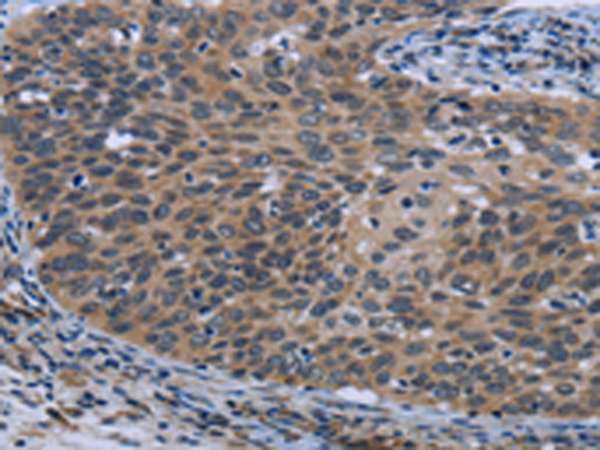

分类: 科研抗体货号: P10717别名: ATG6; VPS30; beclin1应用: WB,IHC反应种属: Human, Mouse, Rat